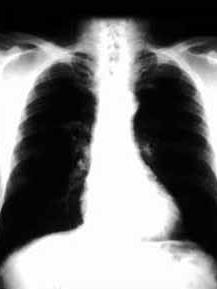

沙雷菌肺炎(serratia pneumonia)是由沙雷菌感染所致,多为医院内获得性感染,近几年来发病率明显增多,且耐药菌株增多,治疗困难。主要表现为发热、寒战、咳嗽、咯血痰或假性血痰或黄痰、呼吸困难、胸痛。现已引起人们广泛注意。[1]